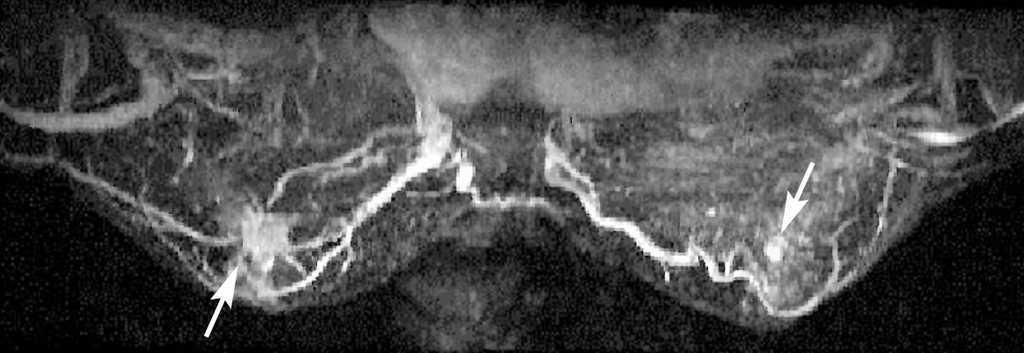

Ante la sospecha de neoplasia mamaria en MD se solicita la realización de una mamografía, ecografía y RM bilaterales. La mamografía muestra unas mamas con tejido fibroglandular de predominio denso con un nódulo espiculado de aproximadamente 1 cm en la LICS de MD. No se aprecian lesiones en MI (fig. 1). La ecografía bilateral confirma la presencia de un nódulo sólido de 1 cm con bordes irregulares, que coincide con la tumoración palpable en la LICS de MD. El estudio de MI no presenta hallazgos significativos (fig. 2). La RM bilateral informa de «... lesión nodular espiculada en LICS de MD con patrón de captación sugestivo de malignidad y que se extiende caudalmente a través de la línea intercuadrántica en presencia de pequeños nódulos satélites con patrones de captación similares que se aproximan hacia el pezón». La lesión nodular principal alcanza unos 14 mm de diámetro mayor, mientras que el conjunto de las lesiones satélites alcanzan unos 15 mm. En MI, «... captaciones significativas en fase arterial con presencia de un pequeño nódulo mal delimitado con un patrón de captación sugestivo de malignidad y con pequeñas lesiones satélite que se extienden caudalmente al igual que en la MD». Estas lesiones están en el cuadrante inferoexterno (CIE), en proximidad de la línea intercuadrántica inferior, a unos 2,5 cm del pezón (fig. 3). Ante el hallazgo de un área sospechosa en la RM de MI se decide solicitar una mamografía magnificada de cuadrantes inferiores de MI, que es informada como normal (fig. 4). Se decide biopsiar con aguja gruesa la masa de MD, y el resultado es de carcinoma ductal infiltrante (CDI) de grado 2.

Figura 3. Resonancia magnética bilateral. Se aprecia una lesión nodular espiculada en línea intercuadrántica (LIC) superior de la mama derecha con patrón de captación sugestivo de malignidad, y que se extiende caudalmente a través de la LIC inferior en presencia de pequeños nódulos satélite con patrones de captación similares (flecha). La lesión nodular principal alcanza unos 14 mm de diámetro mayor, mientras que el conjunto de las lesiones satélite alcanzan unos 15 mm. En la mama izquierda se aprecian captaciones significativas en fase arterial, en presencia de un pequeño nódulo mal delimitado, con un patrón de captación sugestivo de malignidad y varias lesiones satélite que se extienden caudalmente al igual que en la mama derecha. Estas lesiones están en el cuadrante inferoexterno en proximidad de la LIC inferior, a unos 2,5 cm del pezón (flecha).